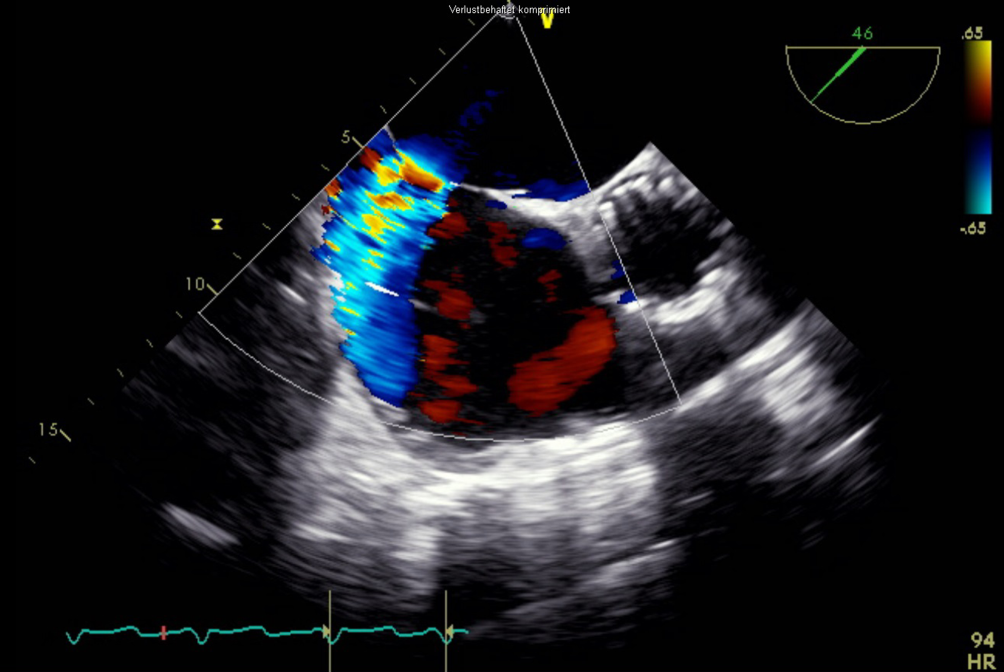

Die endovaskuläre Mitralklappenrekonstruktion wurde unter Vollnarkose begonnen. Der zentrale Venendruck zu Beginn des Eingriffs betrug 12 mm Hg bei einer Sauerstoffsättigung von 100 % und einem Blutdruck von 140/80 mm Hg. Es erfolgten die Punktion der rechten V. femoralis und Einlage einer 7 F-Schleuse mit anschließender transseptaler Punktion und Einlage einer PASCAL Guide Sheath (Edwards Lifesciences, Irvine, CA, USA). Es folgte die erfolgreiche Implantation eines PASCAL-Clips (Edwards Lifesciences) zwischen den Segmenten A2 und P2 (Abb. 3). Es zeigte sich eine adäquate Reduktion der Mitralklappeninsuffizienz nach Clipimplantation mit einer verbleibenden leicht- bis mittelgradigen Insuffizienz (Abb. 4). Die Untersuchung mit dem Continuous-wave-Doppler ergab keinen Hinweis auf eine relevante Stenosewirkung bei einem mittleren Druckgradienten von 4,36 mm Hg.

Abb. 4

Transösophageale Echokardiographie. 2‑D-Ansicht im 4‑Kammer-Blick mit Farbdopplerdarstellung der Mitralklappeninsuffizienz nach PASCAL-Implantation (Edwards Lifesciences)

Bild vergrößern